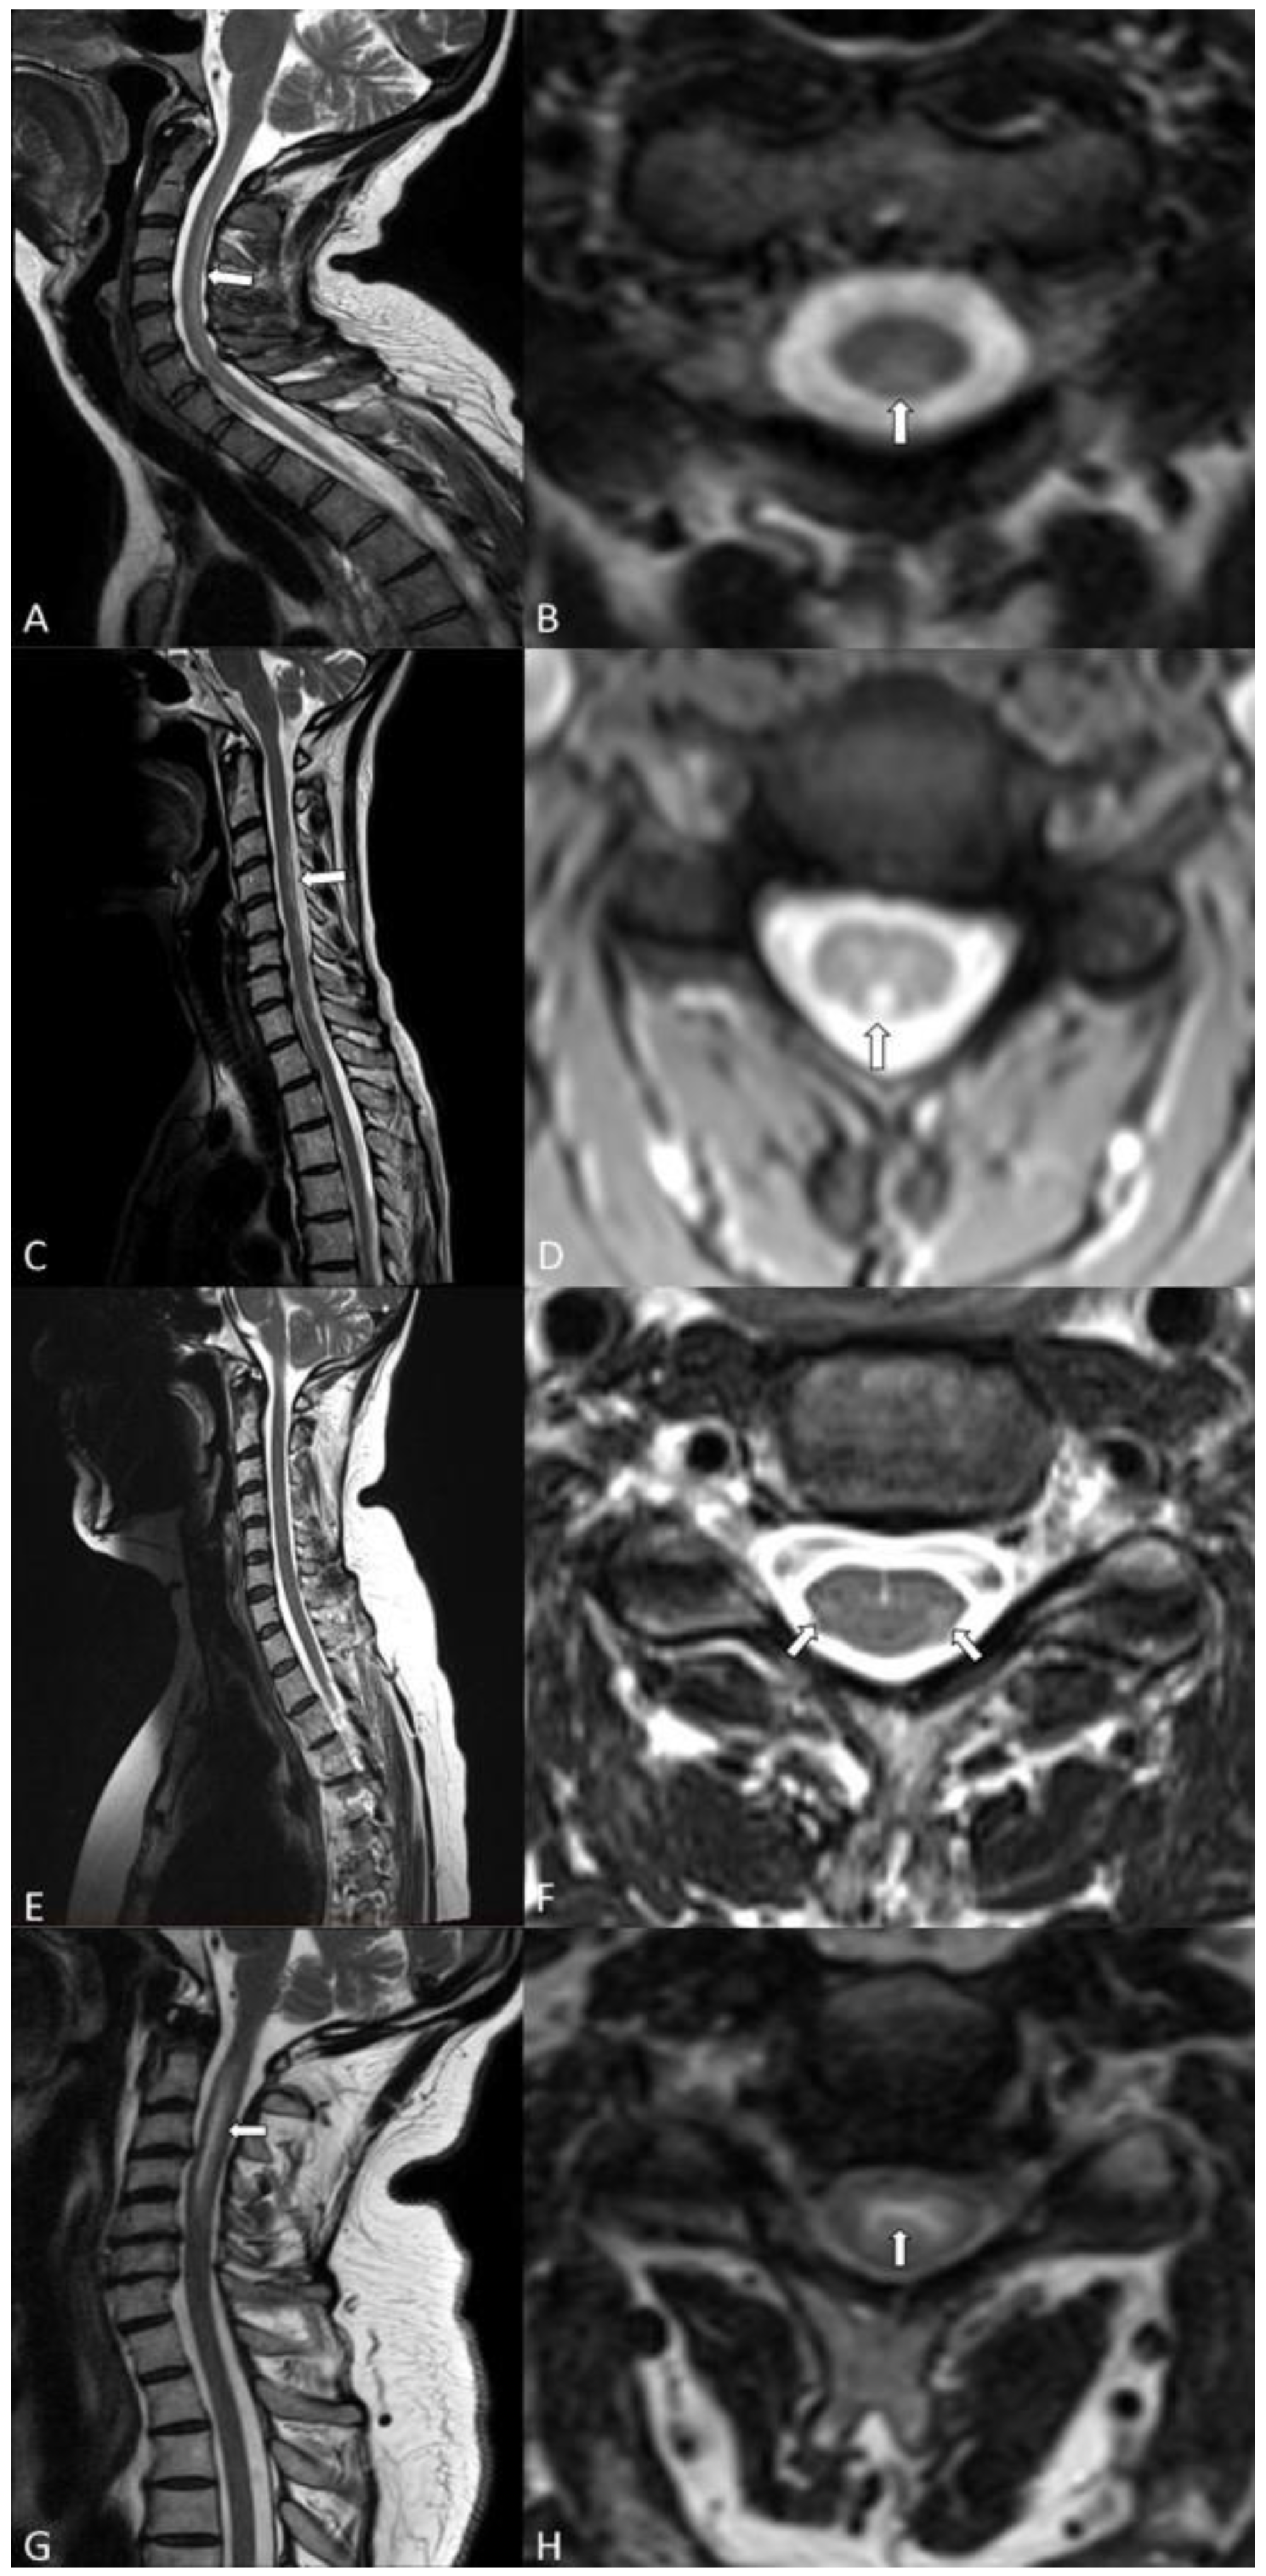

3.6. MRI Pattern

| Extent spinal cord T2 lesion | C3-T5 | C3-C6 | C2-7 | C1-6; T12 |

| Gd+ of spinal cord lesion | no | no | no | yes |